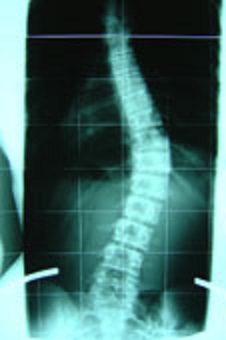

Bezüglich meines Röntgenbildes, ich habe es noch nicht eingescannt, aber ich kann euch schon mal das hier zeigen. Von der Biegung her sieht das bei mir genau so aus, ich erkenne keinen Unterschied.

- Das könnte meine Wirbelsäule sein - sieht genau so aus

- Skoliose 20 GRAD.jpg (17.06 KiB) 11554 mal betrachtet